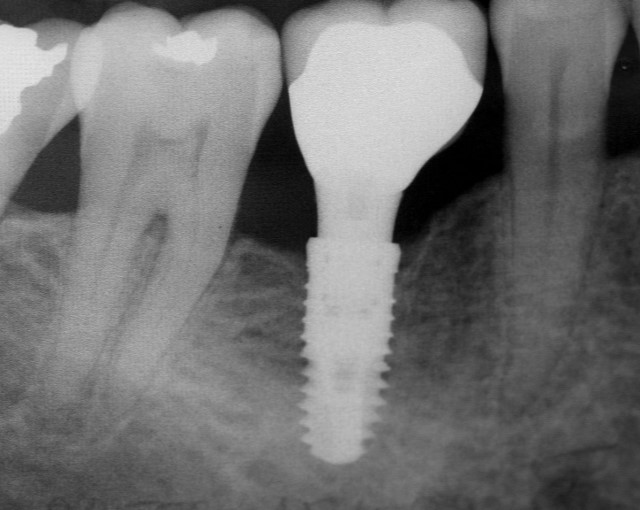

Implantati ali zobni vsadki so torej odlični nadomestki, in sicer v obliki titanovega vijaka. V ustih se jih dopolni s titansko nadgradnjo in kemično prevleko. To je trajna in varna rešitev za nadomeščanje manjkajočih zob.

Implantati se najpogosteje uporabljajo za nadomeščanje enega zoba. Prav tako pa se lahko uporabljajo za nadomeščanje več zob ali celo vseh manjkajočih zob v čeljusti. V tem primeru govorimo o storitvi all on 4. Zobni vsadki so prav tako odlična rešitev za stabilizacijo zobnih protez, in sicer v primeru, da zobna proteza ne omogoča normalnega prehranjevanja.

Implantati se v ustno votlino vstavijo s pomočjo manjšega kirurškega posega. Ta se opravi v lokalni anasteziji in je povsem neboleč. Večina pacientov vam bo povedala, da je puljenje zoba veliko manj prijeten poseg kot pa vstavljanje zobnega vsadka.